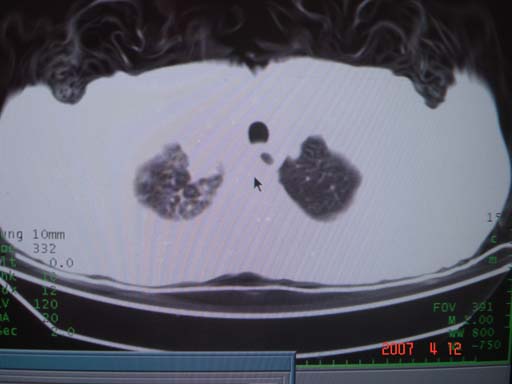

帮我 看看。男77岁咳嗽咯血2月发热2周!病人一般情况可 口痰为鲜红,有点象洗肉水(我看见他吐的痰了)

为何只有这么几幅图像?连纵隔窗都没有。但我发现上叶支气管显示不清,再加上年纪大,咯血等症状,恶性肿瘤首先得考虑。

考虑右肺新生物伴右中上肺阻塞性肺炎及含气不良,右侧胸腔积液。建议痰与纤支镜检查

考虑右侧中央型肺癌伴中上肺阻塞性肺炎、不张,胸腔积液。,建议支纤镜检查。

考虑:右上肺癌伴中上叶炎症,右侧胸腔积液。

病灶局限在右肺中上叶,呈大片状实变影,内见空气支气管征,支气管分支较柔软,纵隔内未见肿大淋巴结.支持:感染性病变_1 大叶性肺炎.2 干酪性肺炎.

优先考虑右上肺干酪性肺炎并同侧中叶播散、胸腔积液。分析:右膈肌未见升高、纵隔未见明显右移,胸部各组淋巴结未见可疑肿大,中叶可见支气管铸形,肺野、肺门未见可确定肿块。

右肺上叶后段支气管中断,首先考虑中央型肺癌并右肺不张及纵隔淋巴结转移,右侧胸腔积液。

有点象洗肉水的痰,其来源应当是实变引起的血细胞渗出导致,可见支气管气象,实变区有虫蚀状空洞,有明显胸腔积液,未见明显肺门区肿块影,考虑继发型肺结核,干酪性肺炎

右肺上叶实变,实变范围如此之大,如果用肺癌解释的化,应该是比较大的支气管开口发生完全阻塞,但观察上叶前后段支气管还是比较通畅,所以应考虑感染性病变,大叶性肺炎可能,建议抗炎治疗后复查。